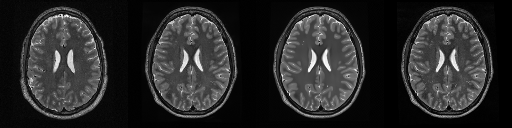

HCP T2w dataset

We utilize images from the publicly available Human Connectome Project (HCP) [51] T2-weighted (T2w) images dataset for the task of compressed sensing, which contains brain images from 47 patients. The HCP dataset includes cross-sectional images of the brain taken at different levels and angles.

Compressed sensing

We train a flow-based model from scratch on 10,000 randomly sampled images, utilizing the ncsnpp architecture [9] with minor adaptations for grayscale images. We employ compression rates , meaning . The measurement operator is given by a subsampled Fourier matrix, whose sign patterns are randomly selected. We evaluate our reconstruction algorithm’s performance on 200 randomly sampled test images.

We present the quantitative and qualitative results of compressed sensing in Tab. 1 and Fig. 4, respectively. As shown in Tab. 1, our method consistently achieves the best performance across varying compression rates . In Fig. 4, our method produces reconstructions that are more faithful to the original images, with fewer artifacts, leading to higher accuracy and clearer details.